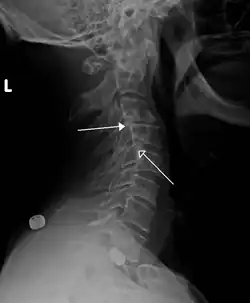

Grade 1 retrolistheses of C3 on C4 and C4 on C5 | |

A retrolisthesis is a posterior displacement of one vertebral body with respect to the subjacent vertebra to a degree less than a luxation (dislocation). Retrolistheses are most easily diagnosed on lateral x-ray views of the spine. Views where care has been taken to expose for a true lateral view without any rotation offer the best diagnostic quality.

Retrolistheses are found most prominently in the cervical spine and lumbar region but can also be seen in the thoracic area.